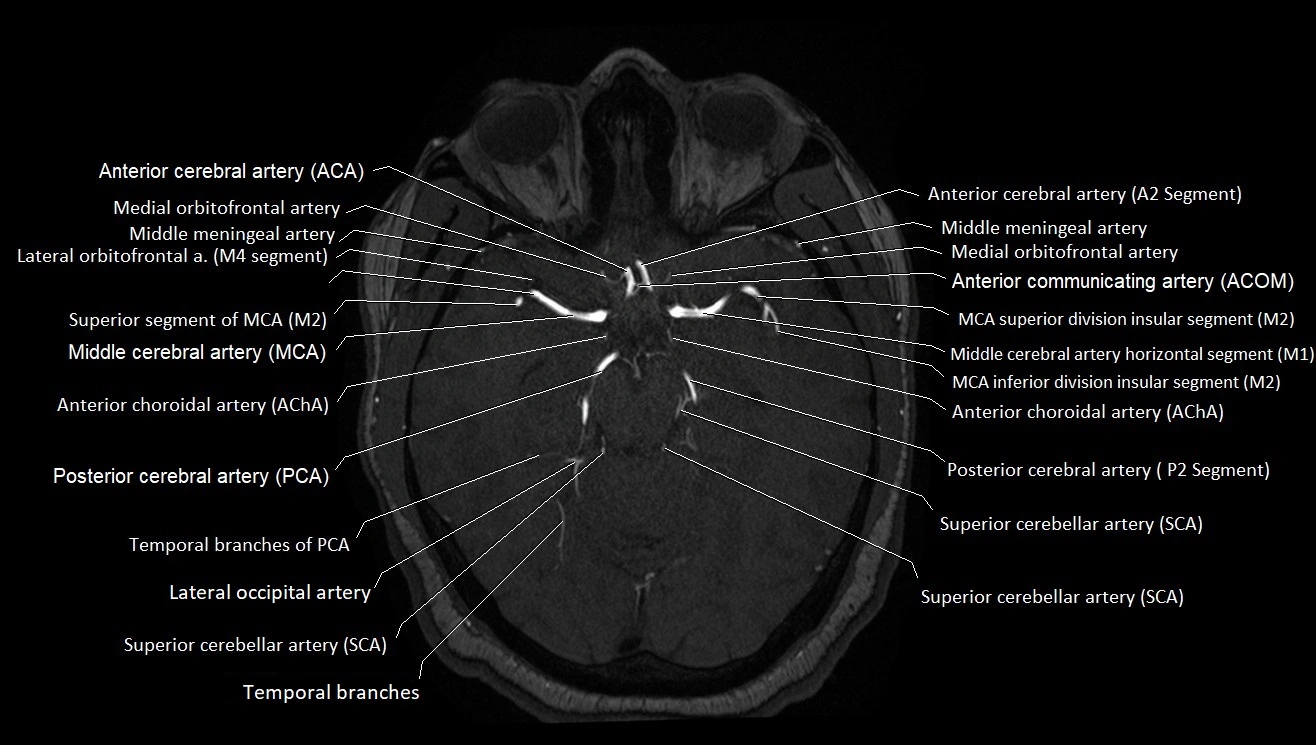

MRA (Magnetic Resonance Angiography):

• Flow-related enhancement makes the AChA appear as a bright, linear vascular signal against suppressed background

• High sensitivity for origin and proximal course; distal branches may be too small to resolve

• Detects stenosis, occlusion, aneurysm, AVM feeders

MRI images

image